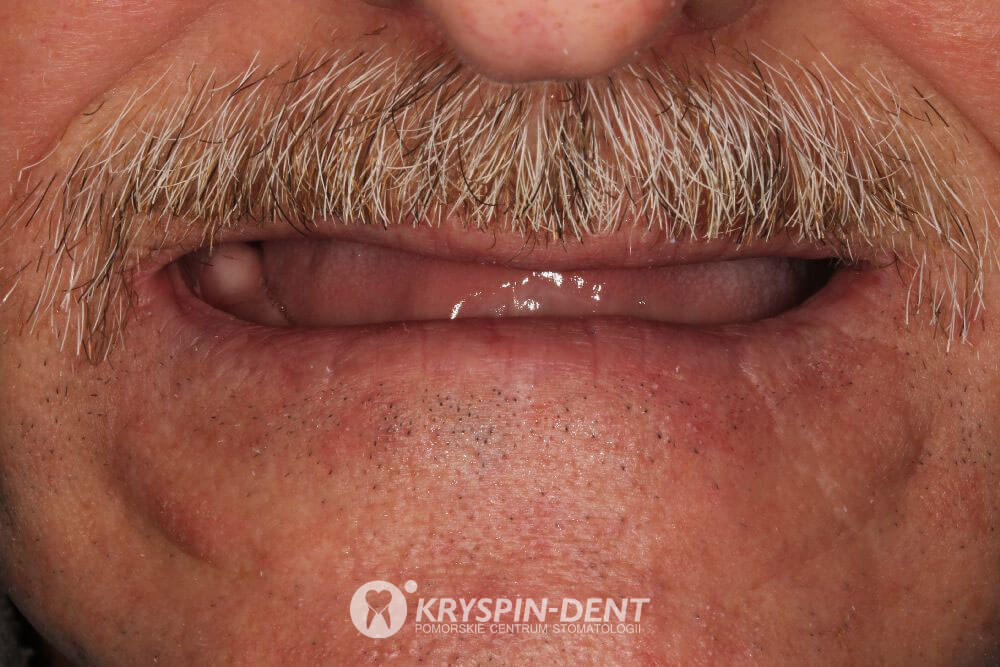

Po

- Dzięki wyjątkowym umiejętnościom pracy lekarzy, laboratorium oraz wysokiej jakości materiałom uzyskano naturalnie wyglądające zęby.

- Pacjent otrzymał nowe, trwałe, wysokoestetyczne i komfortowe w użytkowaniu uzębienie.

- Indywidualnie zaprojektowana, zgodna z kanonem piękna praca protetyczna zapewnia możliwość życia pełnią uśmiechu przez długie lata.

Byłem długi czas pacjentem kliniki Kryspin-Dent i polecam tą klinikę każdemu. Miły personel i bardzo dobrzy lekarze. Jestem bardzo zadowolony z tej kliniki. Chciałem podziękować całemu personelowi, pani doktor Mazurkiewicz i pani doktor Kryspin - profesjonaliści bardzo wysokiej klasy. To co miałem z zębami, a bajeczny efekt końcowy to zasługa pań doktor. Jeszcze raz dziękuję i polecam ta klinikę każdemu.

Po upływie kilku miesięcy wykonano indywidualnie zaprojektowaną, wysokoestetyczną, naturalnie wyglądającą i bardzo komfortową w użytkowaniu, ostateczną pracę protetyczną